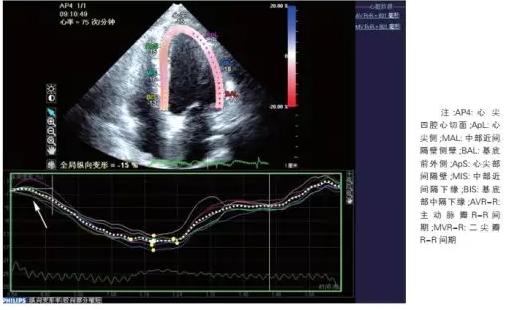

普通心超

令人振奋的是一些新进的研究发现,超声也有可能直接诊断冠心病。来自大连医学院附属大连市中心医院的研究发现,应用二维斑点追踪技术表明,中度以上的冠脉狭窄患者心肌的收缩早期时间明显延长,延迟时间为 60.0 ms可作为诊断值(敏感度为 85.5%,特异度为74.1%,AUC=0.91),该研究发表在《中国循环杂志》上。

图片来源:中国循环杂志

研究者们认为,冠心病时由于部分心肌长期缺血,导致心肌纤维化和心肌肥大,发生心肌重构。当心脏收缩时,左心室压力增高,缺血部分心肌没有足够的主动收缩力来对抗左心室强大的压力,左心室整体纵向收缩功能减低,出现收缩早期的延迟现象。